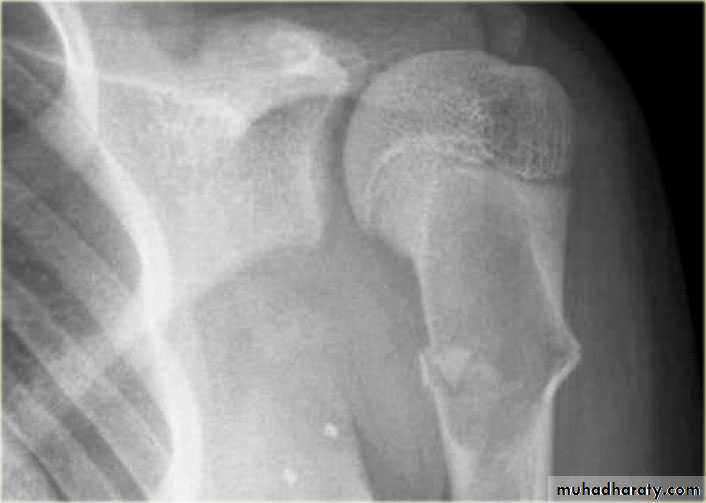

Primary malignant tumoursOsteosarcoma ( osteogenic sarcoma )

Chondrosarcoma :

Ewing sarcoma

Giant cell tumour